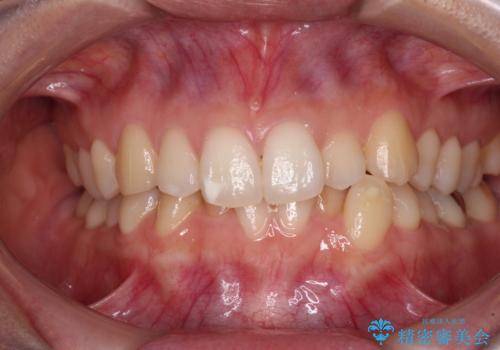

[ 歯を抜かないマウスピース矯正 ] 不揃いの目立つ前歯をきれいにしたい

担当医 大元洋佑

![[ 歯を抜かないマウスピース矯正 ] 不揃いの目立つ前歯をきれいにしたいの症例 治療前](https://seimitsushinbi.jp/wp/wp-content/uploads/2023/08/IMG_9894-500x350.jpg?v=1691028712)